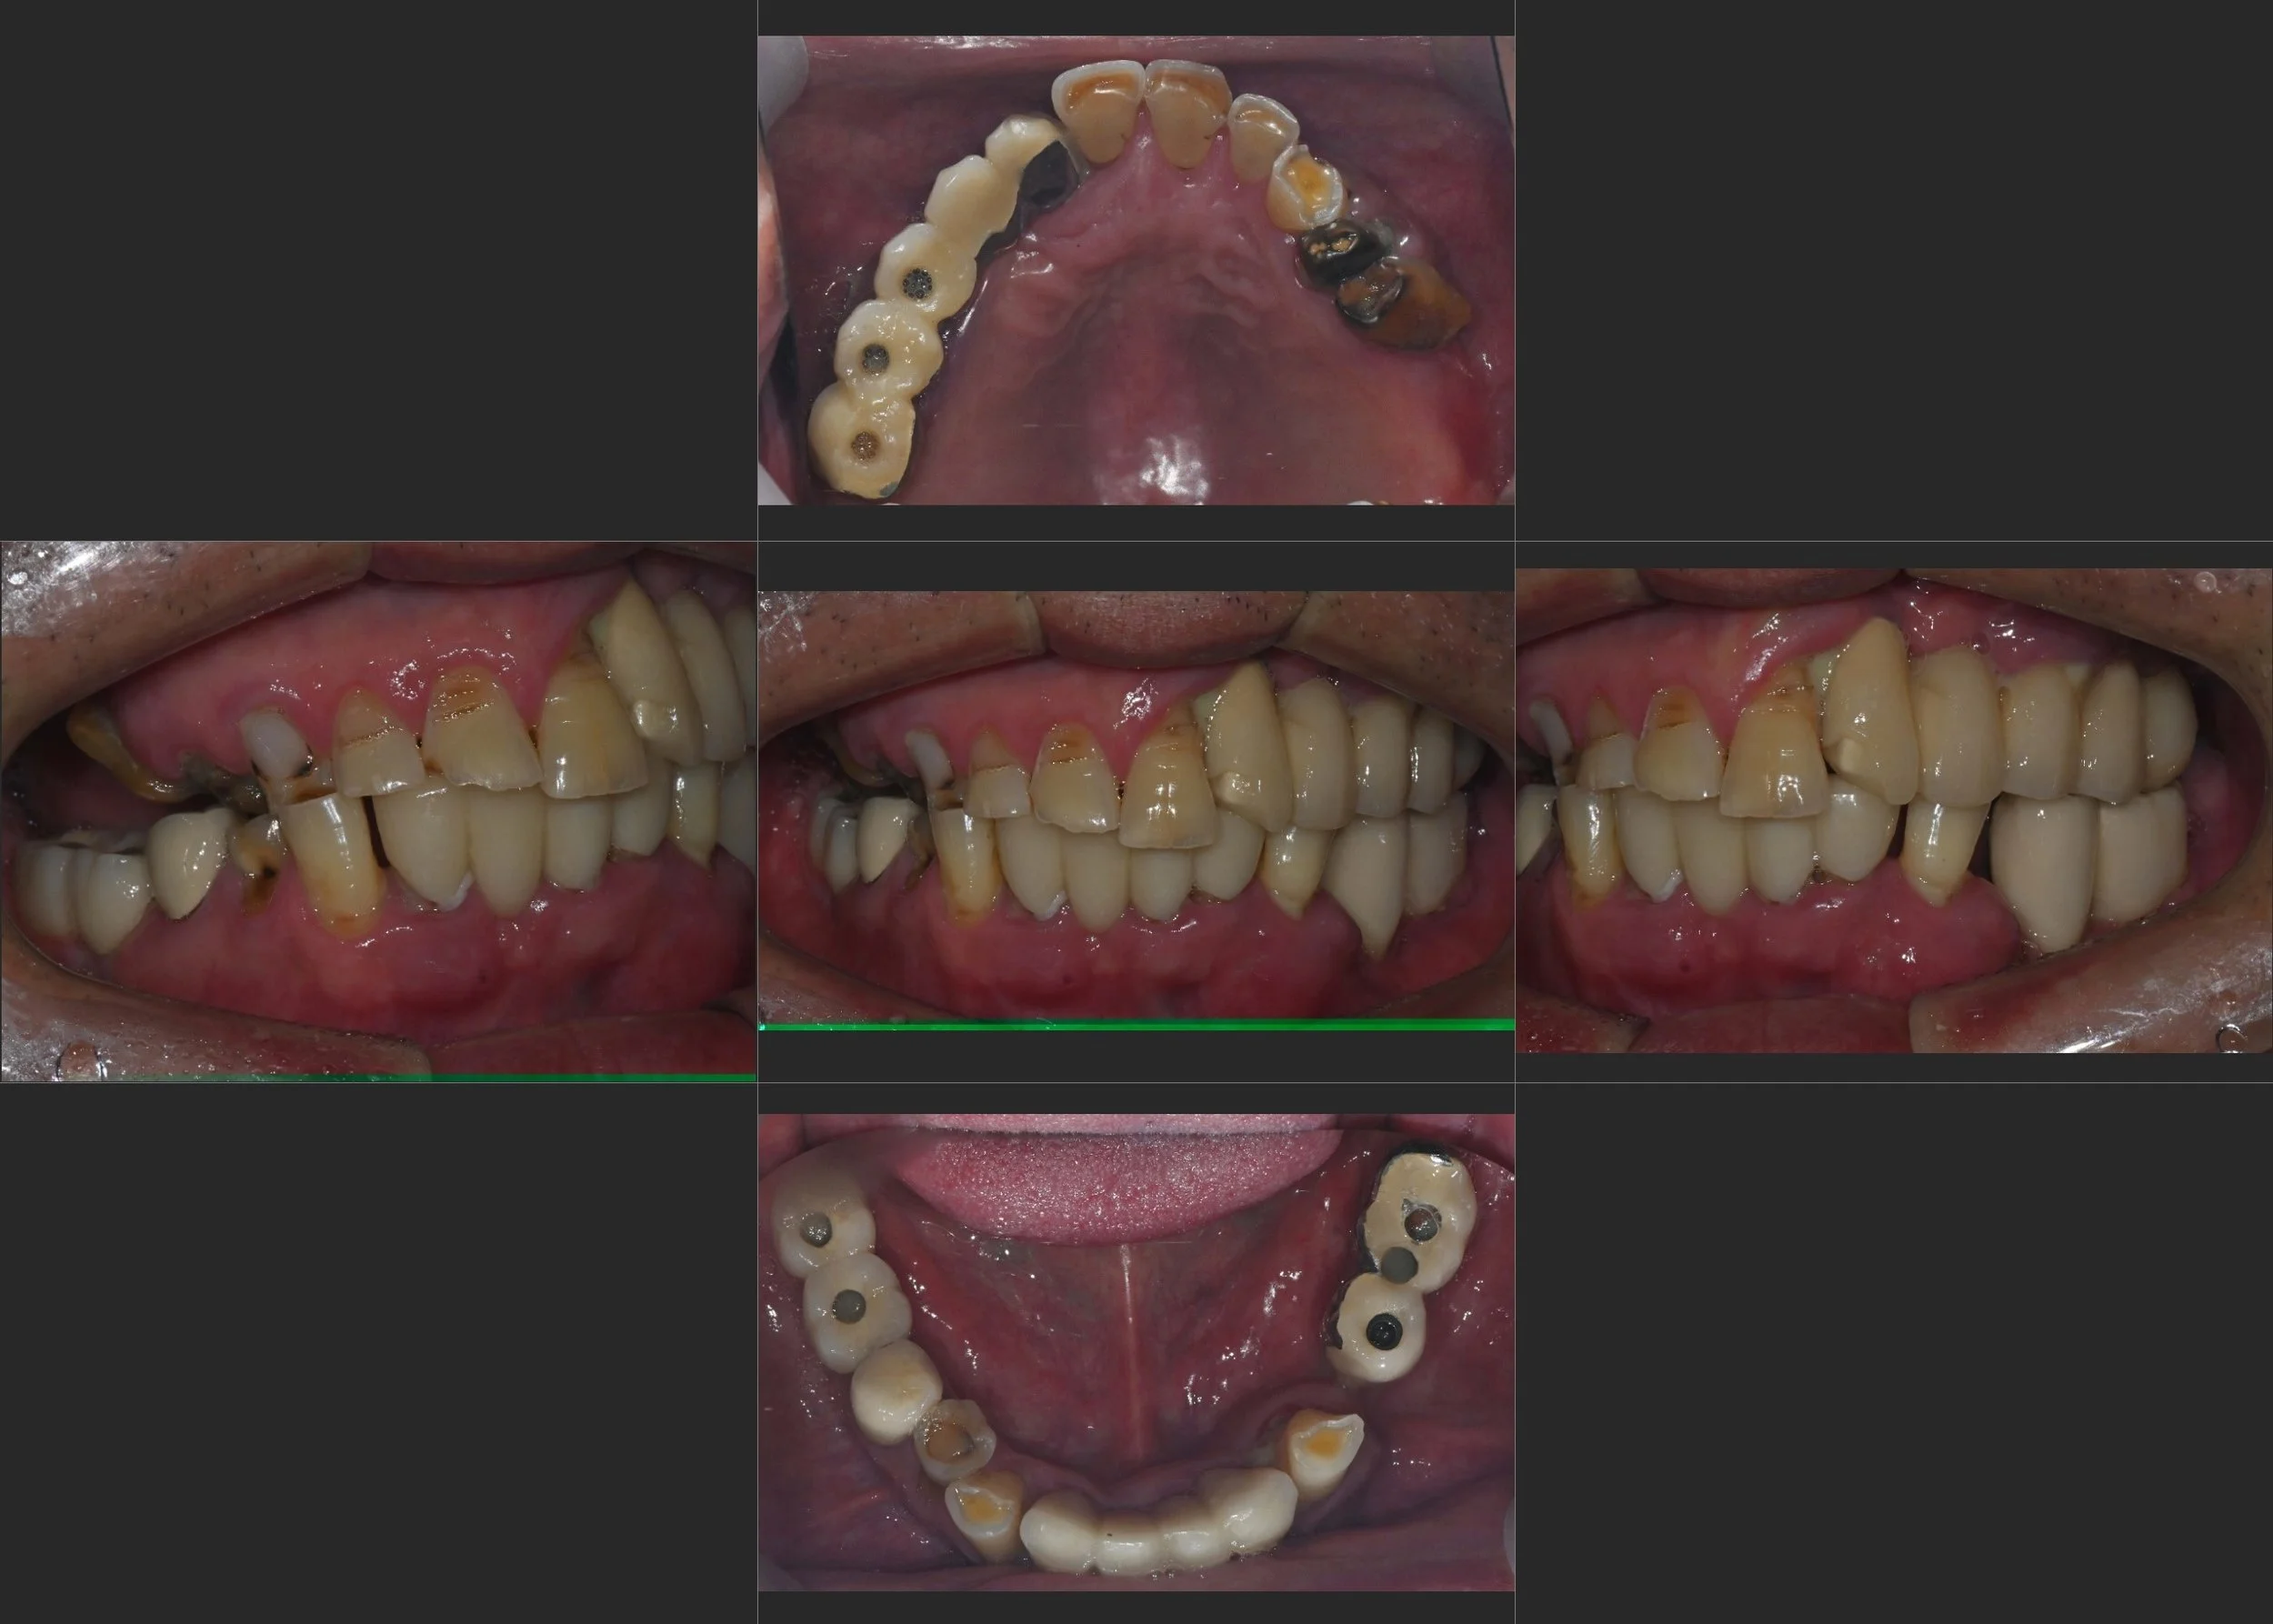

29. Full Mouth Rehabilitation: Restoring Mandibular Position and Occlusal Balance

Correction of Mandibular Retrusion and Anterior Flaring in a Male Patient in his 50s. Re-establishing a predictable balance of forces through posterior implants and non-prep veneers.